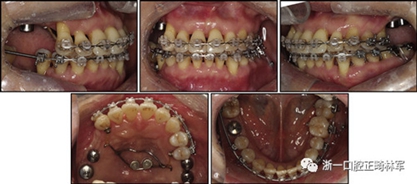

拔除下頜左側(cè)側(cè)切牙,除了4顆前牙外,下頜和上頜牙齒通過0.022英寸的Clippy-C裝置(日本東京的Tomy)粘接聯(lián)合。磨牙管粘結(jié)在下頜磨牙上。排齊過程從0.014英寸的鎳鈦弓絲開始,然后是0.016英寸的鎳鈦弓絲。為了美觀,在拔除的下頜左側(cè)側(cè)切牙間隙中放入一個修復(fù)體。為了防止牙齒的圓形轉(zhuǎn)動,4根上頜前牙被繞過,使牙齒能在尖牙被推向遠中后排齊。將兩個TADs(Orlus,Ortholution,Seoul,Korea)放置在腭板,并且有鉤子附著。將一小段0.016英寸的不銹鋼弓絲放置在上頜左側(cè)尖牙和前磨牙上,并且通過附著在腭板上的鉤子將上頜尖牙和左側(cè)前磨牙推向遠中。

對于近中傾斜和過度萌出的上頜右側(cè)尖牙,需要控制牙齒向遠中傾斜和向下推入。用兩個鉤子在兩側(cè)施加不同方向的力,以期望右側(cè)尖牙的推入(圖7)。在上頜尖牙遠中移動后,用一根0.014英寸的鎳鈦弓絲將4顆上頜前牙排齊。放置逐漸變硬的弓絲,直到上下兩個牙弓都放置0.017*0.025英寸的不銹鋼弓絲。然后關(guān)閉下頜前牙區(qū)間隙,用完全相同的力學(xué)原理將上頜全牙列向遠中移動,以獲得適當?shù)母埠虾透采w。此外,還有一個0.017*0.025英寸β-鈦絲的直立彈簧應(yīng)用于下頜右側(cè)第二磨牙。當直立彈簧接合到主弓絲上時,引起前磨牙的推入,第二磨牙的推出,前磨牙的頰側(cè)傾斜以及第二磨牙的舌側(cè)傾斜,以矯正牙弓形態(tài)(圖8)。

圖7. 用TAD將上頜牙齒推向遠中。兩個附著在TAD上不同方向的鉤子

圖8. 在主弓絲中的下頜第二磨牙的直立彈簧

由于患者有多個缺失的后牙,因此考慮到具有垂直方向的喪失。然而,她在拔除后牙后立即去正畸科就診。她封閉了天然的左側(cè)前磨牙,并且沒有前牙的咬合磨損。因此,垂直維度被維持是確定的。在正畸治療過程中,牙種植體植入在上頜后牙區(qū)和下頜右側(cè)第一磨牙的位置(圖9)。經(jīng)過3個月的骨結(jié)合后,種植體用臨時冠修復(fù)以支持垂直維度。

圖9. 上頜牙齒推向遠中,糾正下頜左側(cè)磨牙的傾斜度,并放入種植體